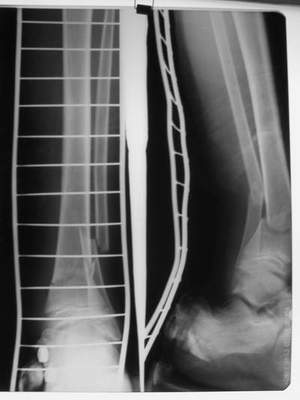

Промежуточный

A> Это сросшийся перелом малоберцовой кости. И ложный сустав

A> н\3 б\берцовой кости.

Таперича это ясно.

А аппаратами пользуетесь?

Нашел в комп-ре схожий случай:

1) з/репозиция, 2) фиксация 2 спицами, 3) аппарат, 4) фиксационные

спицы удалены...

См. аттачт.

А можно было наложить аппарат и по поводу ложного сустава...

По крайней мере не было бы укорочения (пусть и в 2 см)...